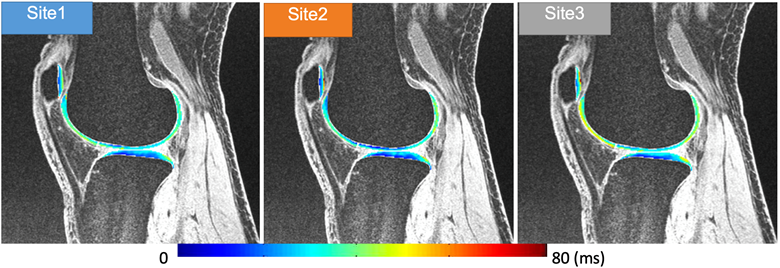

Multi-vendor Multi-site Novel Accelerated MRI Relaxometry

PI: Xiaojuan Li, PhD

Co-Is: Carl Winalski, MD; Kunio Nakamura, PhD; Nancy Obuchowski, MD; Erika Schneider, PhD; Kurt Spindler, MD; Morgan Jones, MD

External Collaborators: Leslie Ying, PhD (New York State Univ. at Buffalo); Peter Hardy, PhD (Univ. of Kentucky); Thomas M. Link, MD; Jing Liu, PhD (UCSF PI); Chris Peng, PhD (Einstein College of Medicine); Kathryn Keenan, PhD (NIST); Elizabeth Mirowski, PhD (Verellium); Ravinder Reddy, PhD (Univ. Penn); Brian Hargreaves, PhD (Stanford Univ)

Funding Sources:Arthritis Foundation; NIH/HIAMS R01 AR077452

Abstract:

MR T1ρ and T2 relaxation times have shown to be promising imaging biomarkers for early cartilage degeneration, and prediction of disease progression. However, many challenges to clinically applying these techniques remain, including lack of standardized acquisition and quantification methods, and long acquisition time. We have implemented MAPSS T1ρ and T2 imaging sequences on three major MR platforms (Siemens, GE and Philips) and have performed multisite multivendor cross validation and reproducibility evaluation, sponsored by the Arthritis Foundation. The next step is to develop fast T1ρ and T2 imaging techniques using novel MRI reconstruction and evaluate the reproducibility and clinical significance of the technique in a multivendor multicenter setting in volunteers and patients with osteoarthritis. A dedicated MSK calibration phantom will be also developed.